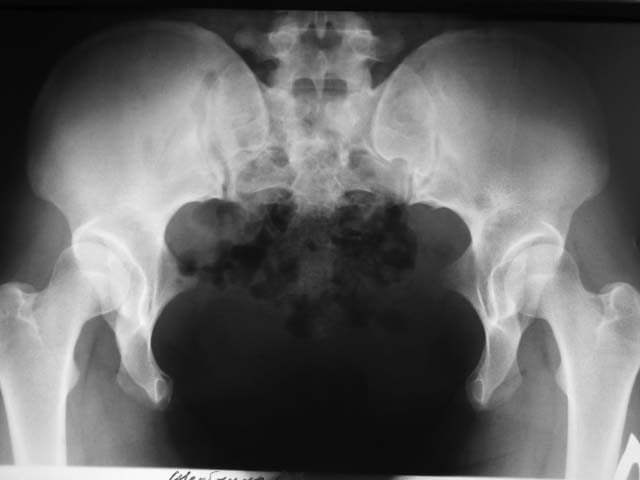

Пациентке 23 года. Деформация врожденная. Беспокоят умеренные боли в задних отделах таза

после длительной ходьбы. Ходит - не хромает. Деформация стабильная. Что делать? И делать

ли...